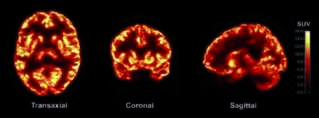

Heinous crimes tend to defy comprehension, but some researchers believe neuroscience and genetics could help explain why certain people commit such atrocities. Meanwhile, lawyers are introducing so-called neurobiological evidence into court more than ever in an effort that may challenge long-held understandings of justice, personal responsibility and free will.